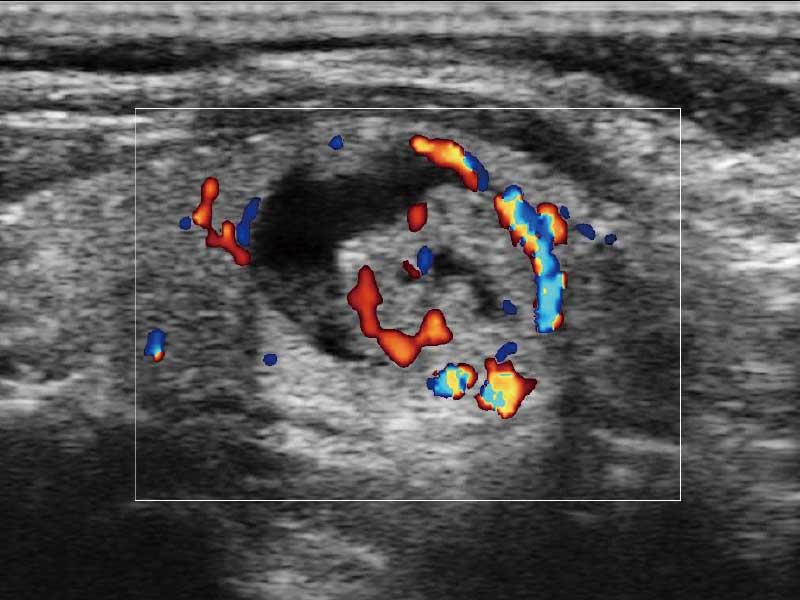

E2便携式彩色多普勒超声诊断系统采用专业的超声技术平台、高度集成化的硬件模块和结构设计、简便的操作流程、多探头接口设计,兼顾了优质图像、轻便机身以及台便两用的临床使用需求。

μ-Scan微米成像、空间复合成像、高分辨率血流成像。